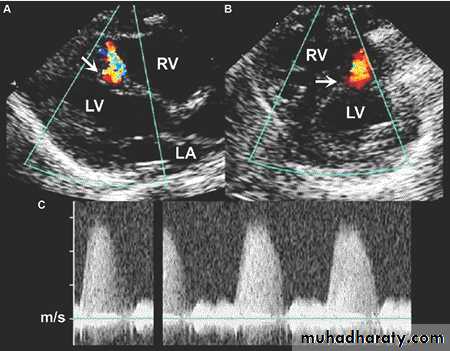

PLAX & PSAX views of echo showing muscular VSD

A5C view echo showing membranous VSDVENTRICULAR SEPTAL DEFECT (cont.)

VSD …Echo